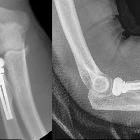

Elbow arthroplasties are an increasingly common joint replacement, most often used for treatment of late stage rheumatoid arthritis, but which may also be used as a treatment for late stage osteoarthritis or complex fractures of the proximal radius, proximal ulna, or distal humerus.

- radial head replacement

- for complex radial head fractures

Imaging evaluation usually requires AP and lateral views, and focuses on looking for loosening or periprosthetic fracture:

- "loose-fit" components in some radial head replacements have an expected 2 mm lucent rim around the prosthesis

- "press-fit" components do not have a lucent rim

The radial head may be resected when placing the arthroplasty.